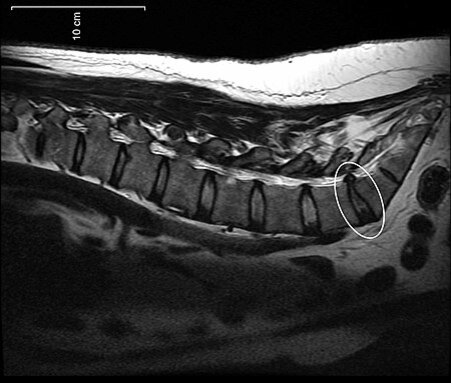

Рыбная кость в горле